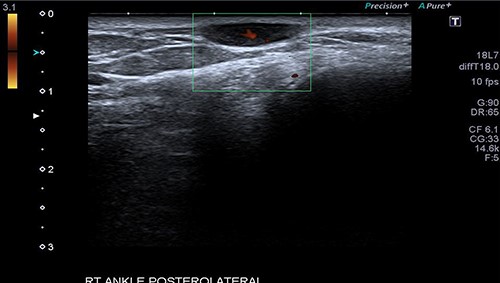

A 34-year-old gentleman presented with a swelling over the posterolateral aspect of his right ankle close to the Achilles tendon. He complained of pain and sensitivity to wearing shoes. The swelling was 10 × 5 mm, mobile and ultrasound (US) scan reported it as ‘A well-defined ovoid hypoechoic lesion underneath the skin surface measuring approximately 11 mm × 3 mm in diameter and appears related to a linear hypoechoic structure’ (Fig. 1). ‘The lesion is slightly heterogeneous in texture and shows posterior acoustic enhancement on the underlying tissues. There is mild internal vascularity of this lesion on Doppler assessment’ (Fig. 2) and ‘these appearances are suggestive of superficial neuroma lesion’. Post-excision, the histology of a single piece of pale smooth firm tissue (9 × 6 × 5 mm) was reported as angioleiomyoma. He made an uneventful recovery and was discharged after 4 months of follow-up.

The US scan image of the right ankle posteriolateral aspect of Patient 1, which showed a well-defined ovoid hypo echoic lesion underneath the skin surface; measuring ~11 × 3 mm in diameter.

An arteriogram or Doppler study may be useful to an extent, but a confirmed diagnosis is only obtained through histopathological examination after excision [8–10]. Case 1 had an US scan of the swelling which showed a well-defined ovoid hypoechoic lesion underneath the skin surface, and the lesion was slightly heterogeneous in texture and shows posterior acoustic enhancement on the underlying tissues. There was mild internal vascularity of this lesion on Doppler assessment—appearances suggestive of superficial neuroma lesion. The usual appearance of these lesions on USS is a well-circumscribed oval mass with a homogenous echotexture and occasionally hypoechoic protrusions.